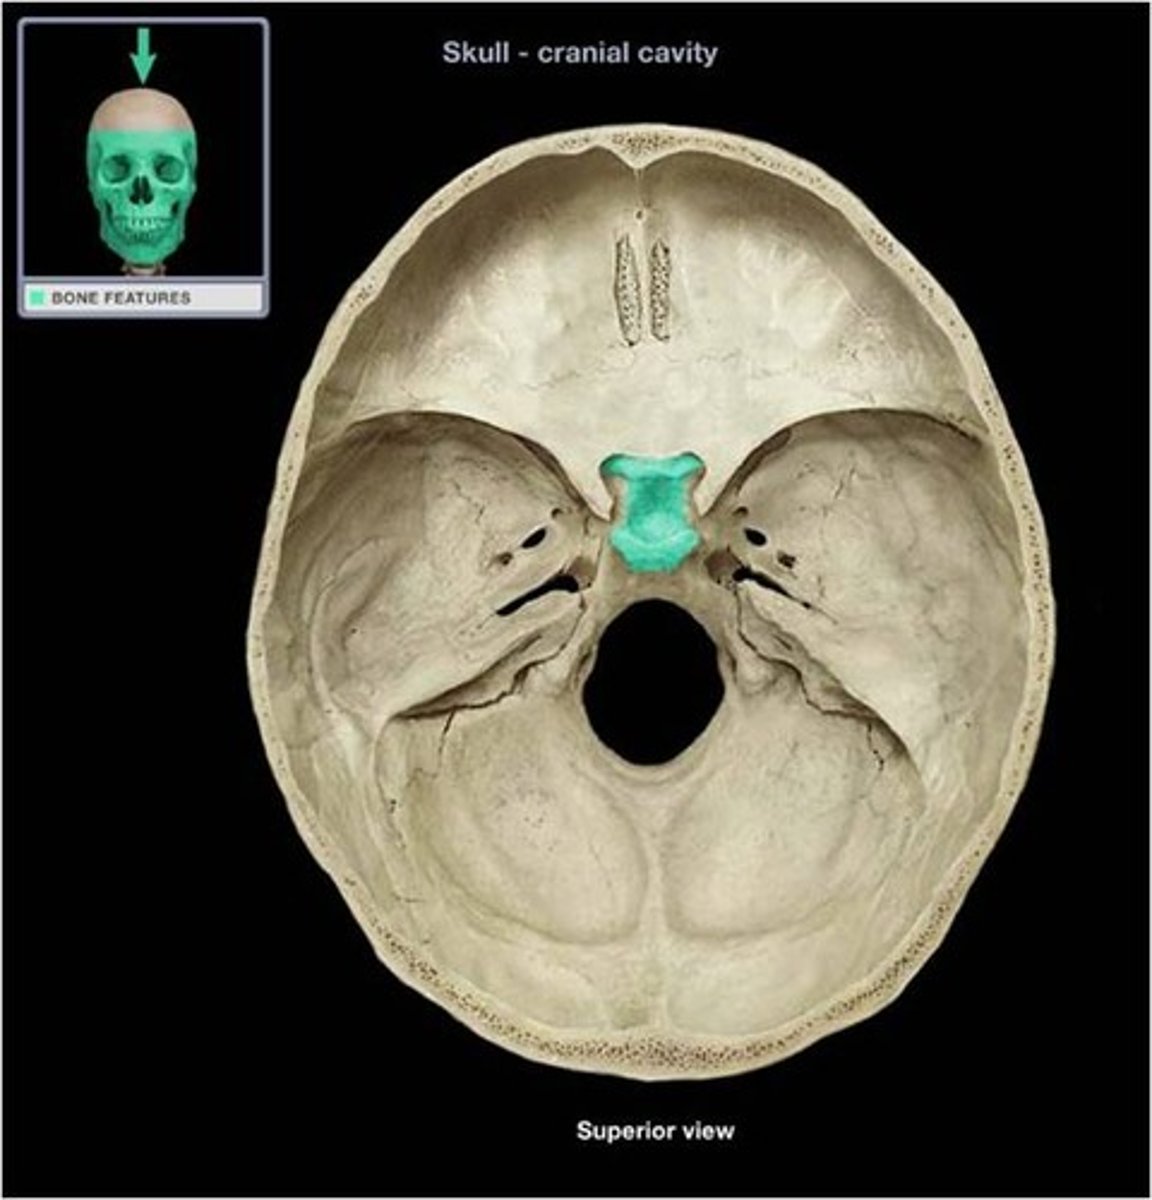

Sphenoid

Name the bone.

sella turcica

Name this structure.